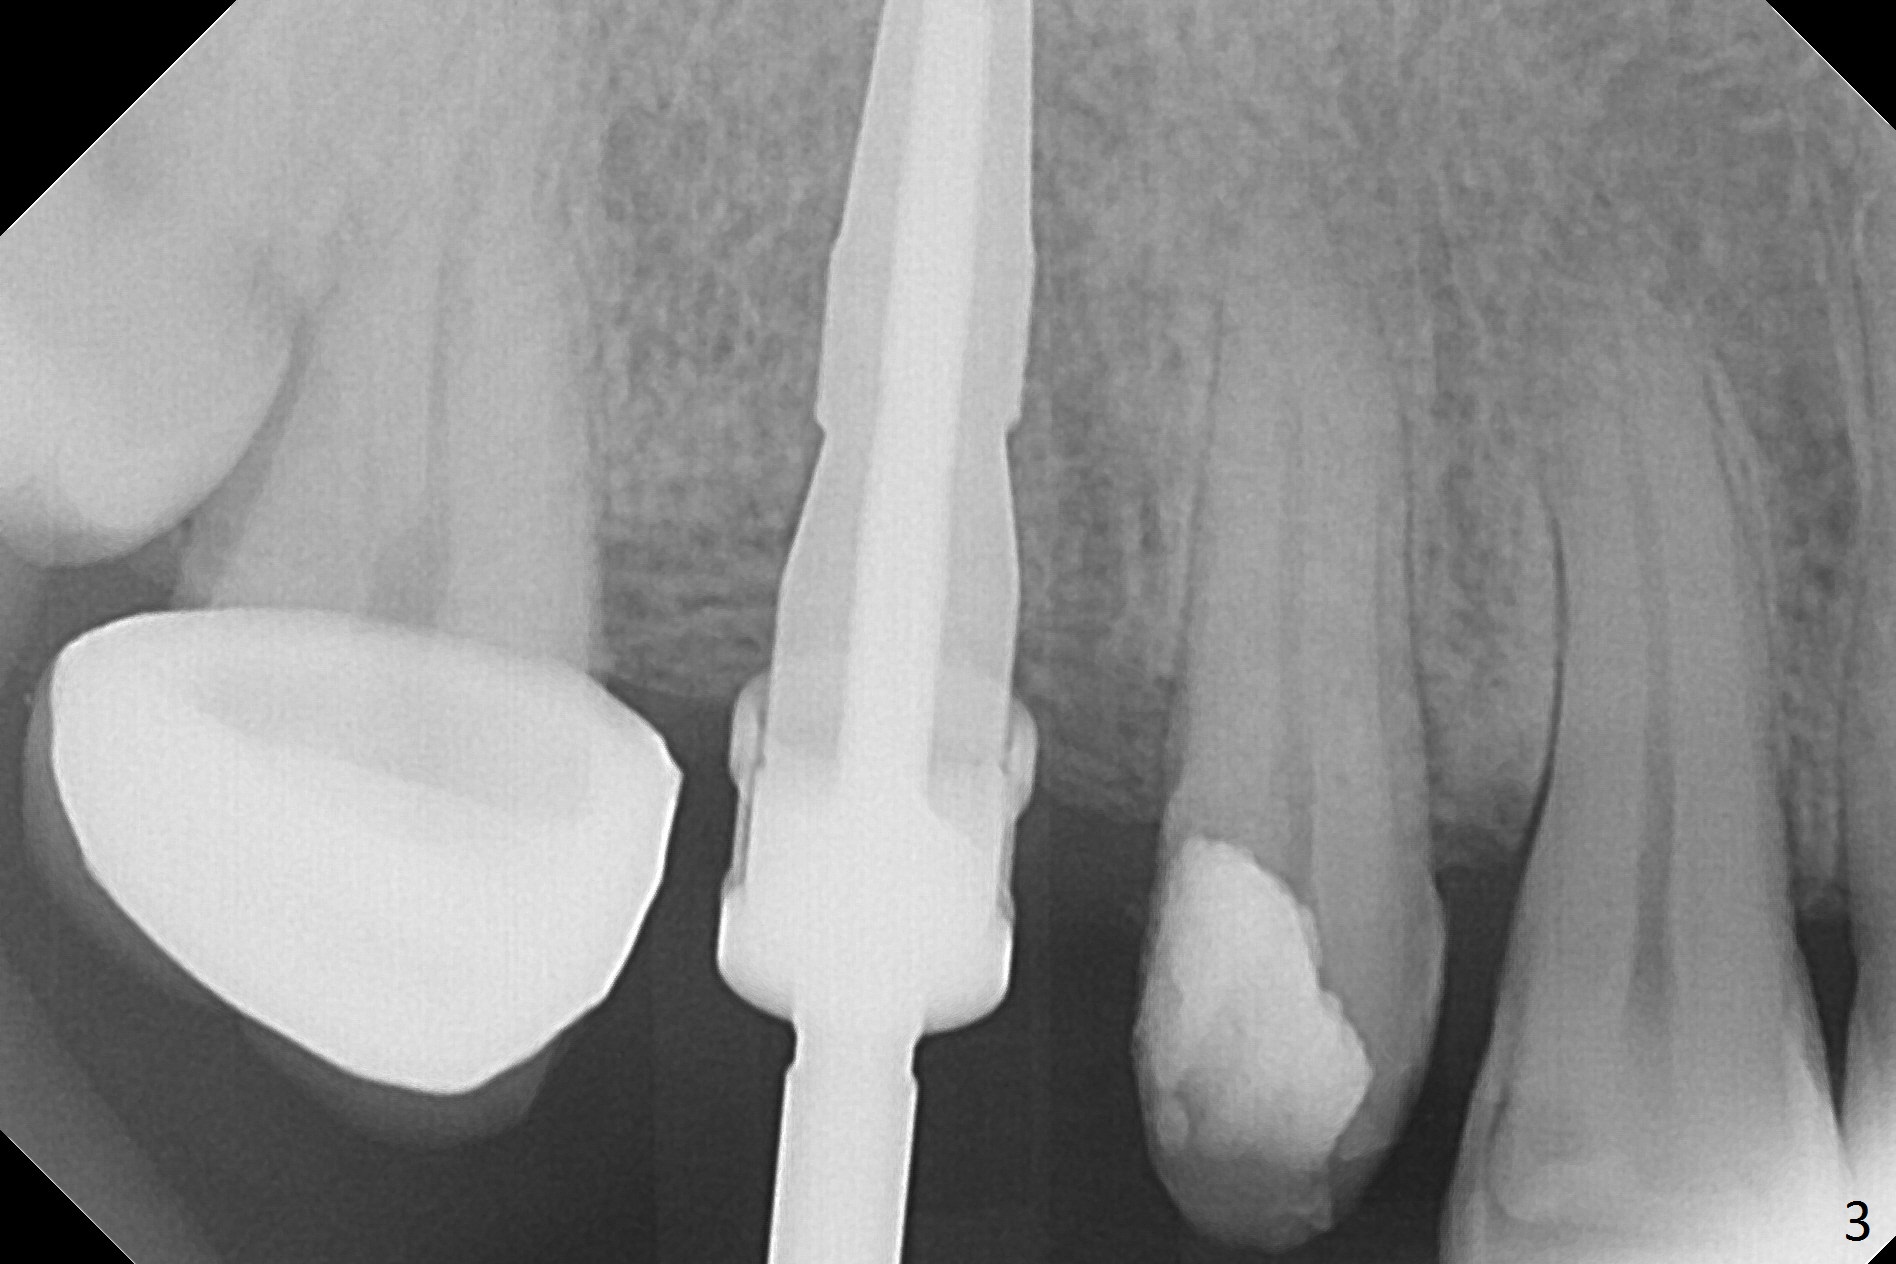

When the bridge is partially removed, the tooth #4 is found to have extensive caries. IRM is placed following carious removal (Fig.1). Magic Split testing shows that the bone density is high (flapless). Osteotomy is initiated by 1.6 mm drill, but the handle of the drill needs to shift mesial (Fig.1 red arrow). When the latter is done, the whole drill (2 mm) needs to move distal (Fig.2 double red arrows). When a 4.5x14 mm drill finishes the osteotomy, it is in the middle of the edentulous space (Fig.3). After use of 5 mm tap, a 5.3x14 mm implant cannot reach the depth (Fig.4,5). Following increase in osteotomy depth from 16 to 18 mm (gingival margin) until 5 mm drill in diameter, the implant placement level is more ideal (Fig.6,7, slightly subcrestal) with insertion torque maintaining at >55 Ncm. The sinus floor (Fig.4 arrowheads) may be penetrated when the osteotomy depth increases (Fig.7 *), but the sinus membrane remains intact.